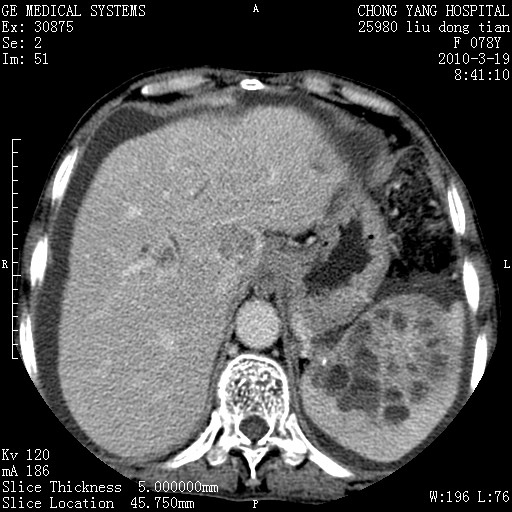

标题: CT25199:F 78Y 腹胀半年 消瘦乏力 [打印本页]

胆囊壁增厚并明显强化,胆囊癌伴多发转移瘤可能性大,淋巴瘤不除外,右肾囊肿,胸腹水.

考虑nhl,肝、脾、腹膜腔及腹膜后多发淋巴结受侵,腹水,右肾囊肿,慢性胆囊炎,右侧少量胸腔积液。

胆囊有软组织影有强化,支持胆囊癌,肝脾、腹膜后淋巴结转移。

nhl的淋巴结多围绕主动脉,而且主动脉会移位,所以不考虑nhl。

分开来讲:肝左叶、尾叶病灶有不均强化像肝癌;

脾脏病灶无强化,像多发囊肿或淋巴管瘤,不除外淋巴瘤(低强化);

胆囊增生性病变:胆囊癌,腺肌增生症,慢性胆囊炎;

肝门、胰腺头、腹膜后多个团块: 淋巴瘤,转移;

腔静脉肝内段细小有无布加可能?

一元论最好了 淋巴瘤所致改变; 胆囊癌转移不像,胆囊周围肝组织清晰,肝癌淋巴结转移?三元论都不止。

脾脏病灶像车轮 莲花,第一感觉还像包虫呢。真想全切出来一个个做病检。

最后报的胰头癌多发转移,脾脏单独考虑囊肿或淋巴管瘤。